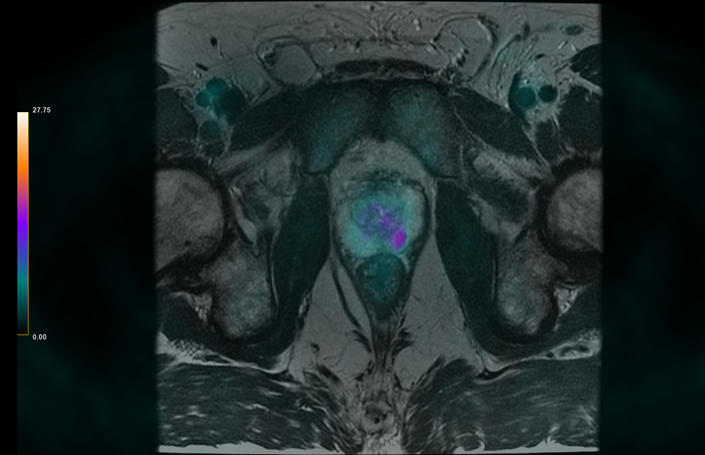

Tras la inclusión, el equipo de ingeniería I+D de Ascires realiza un estudio radiómico sobre la lesión del paciente, siempre bajo la supervisión de un médico especialista en radiología para asegurar que la segmentación tiene la máxima calidad para el estudio. Una vez segmentada la lesión, se extraen las características radiómicas sobre la secuencia potenciada en T2, el PET y en los mapas ADC provenientes de la secuencia de difusión (ADC). Estas características serán introducidas en la base de datos del proyecto ADUR junto a el resultado de la biopsia del paciente y la PSA (Antígeno Prostático Específico).